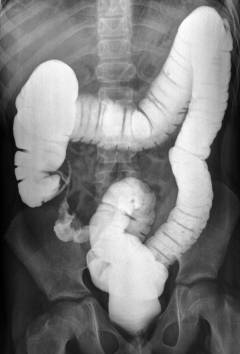

Ирригография

рентгенконтрастное исследование прямой и толстой кишки

Ирригография – рентгеновские снимки прямой  кишки, выполненные после того, как в нее введено контрастное вещество (взвесь сульфата бария).

Ирригоскопия – рентгенологическое исследование, при котором заполненную контрастом прямую кишку осматривают в режиме реального времени на экране.

Проведение ирригографии:

• врач вводит пациенту в прямую кишку взвесь сульфата бария при помощи клизмы;

• выполнятся снимки в разных проекциях;

• после опорожнения прямой кишки на ее стенках все еще остается немного контрастна – можно сделать дополнительные снимки и осмотреть рельеф.

Что выявляется во время ирригографии:

• объемные образования на стенке прямой кишки: контраст обтекает их, образуется так называемый «дефект наполнения»;

• размеры и протяженность образования;

• наличие на стенке язвенных дефектов;

• характер роста опухоли: наружу или внутрь, в стенку кишки.